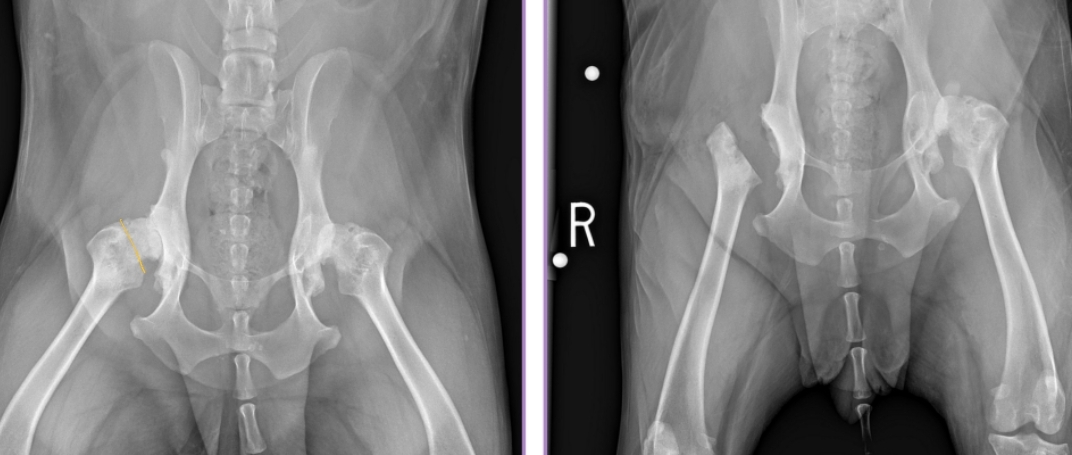

Pathogenesis of Hip Dysplasia

Dev: Abnormal development of the coxofemoral joint

Subluxation + Osteoarthritis (DJD)

#1 dz of the coxofemoral joint

Primary: genetic, Environmental: contributing

Et: Round lig and joint capsule are stretched → subluxation of femoral head

Phase 1: excessive joint lax → phase 2: osteoarthritis

Cartilage damage, Trabecular bone microfracture, Synovitis

Risk: Genetics, rapid weight gain or growth, high Ca + protein diet, activity, flooring, decreased pelvic muscle mass, large breeds

Clinical Presentation of Hip Dysplasia

Bilateral > unilateral

<6-8 months: Abnormal gait, Bunny hopping, Asymmetric sitting, Waddling, Reluctant to jump, Mildly painful

6-12 months: unilateral/bilateral Hind limb lameness, Difficulty rising, Exercise intolerance, Stiff gait, Thigh muscle atrophy, Pain, Decreased muscle mass

10-12 months: Fxn improvement, Joint capsule fibrosis and tightening, Residual lameness

Long-Term: Lameness, Thigh muscle atrophy, Crepitus, Pain, Chronic low-grade OA, circumduction, hopping

lameness worse in AM & after exercise

32% of dogs will also have CrCL rupture